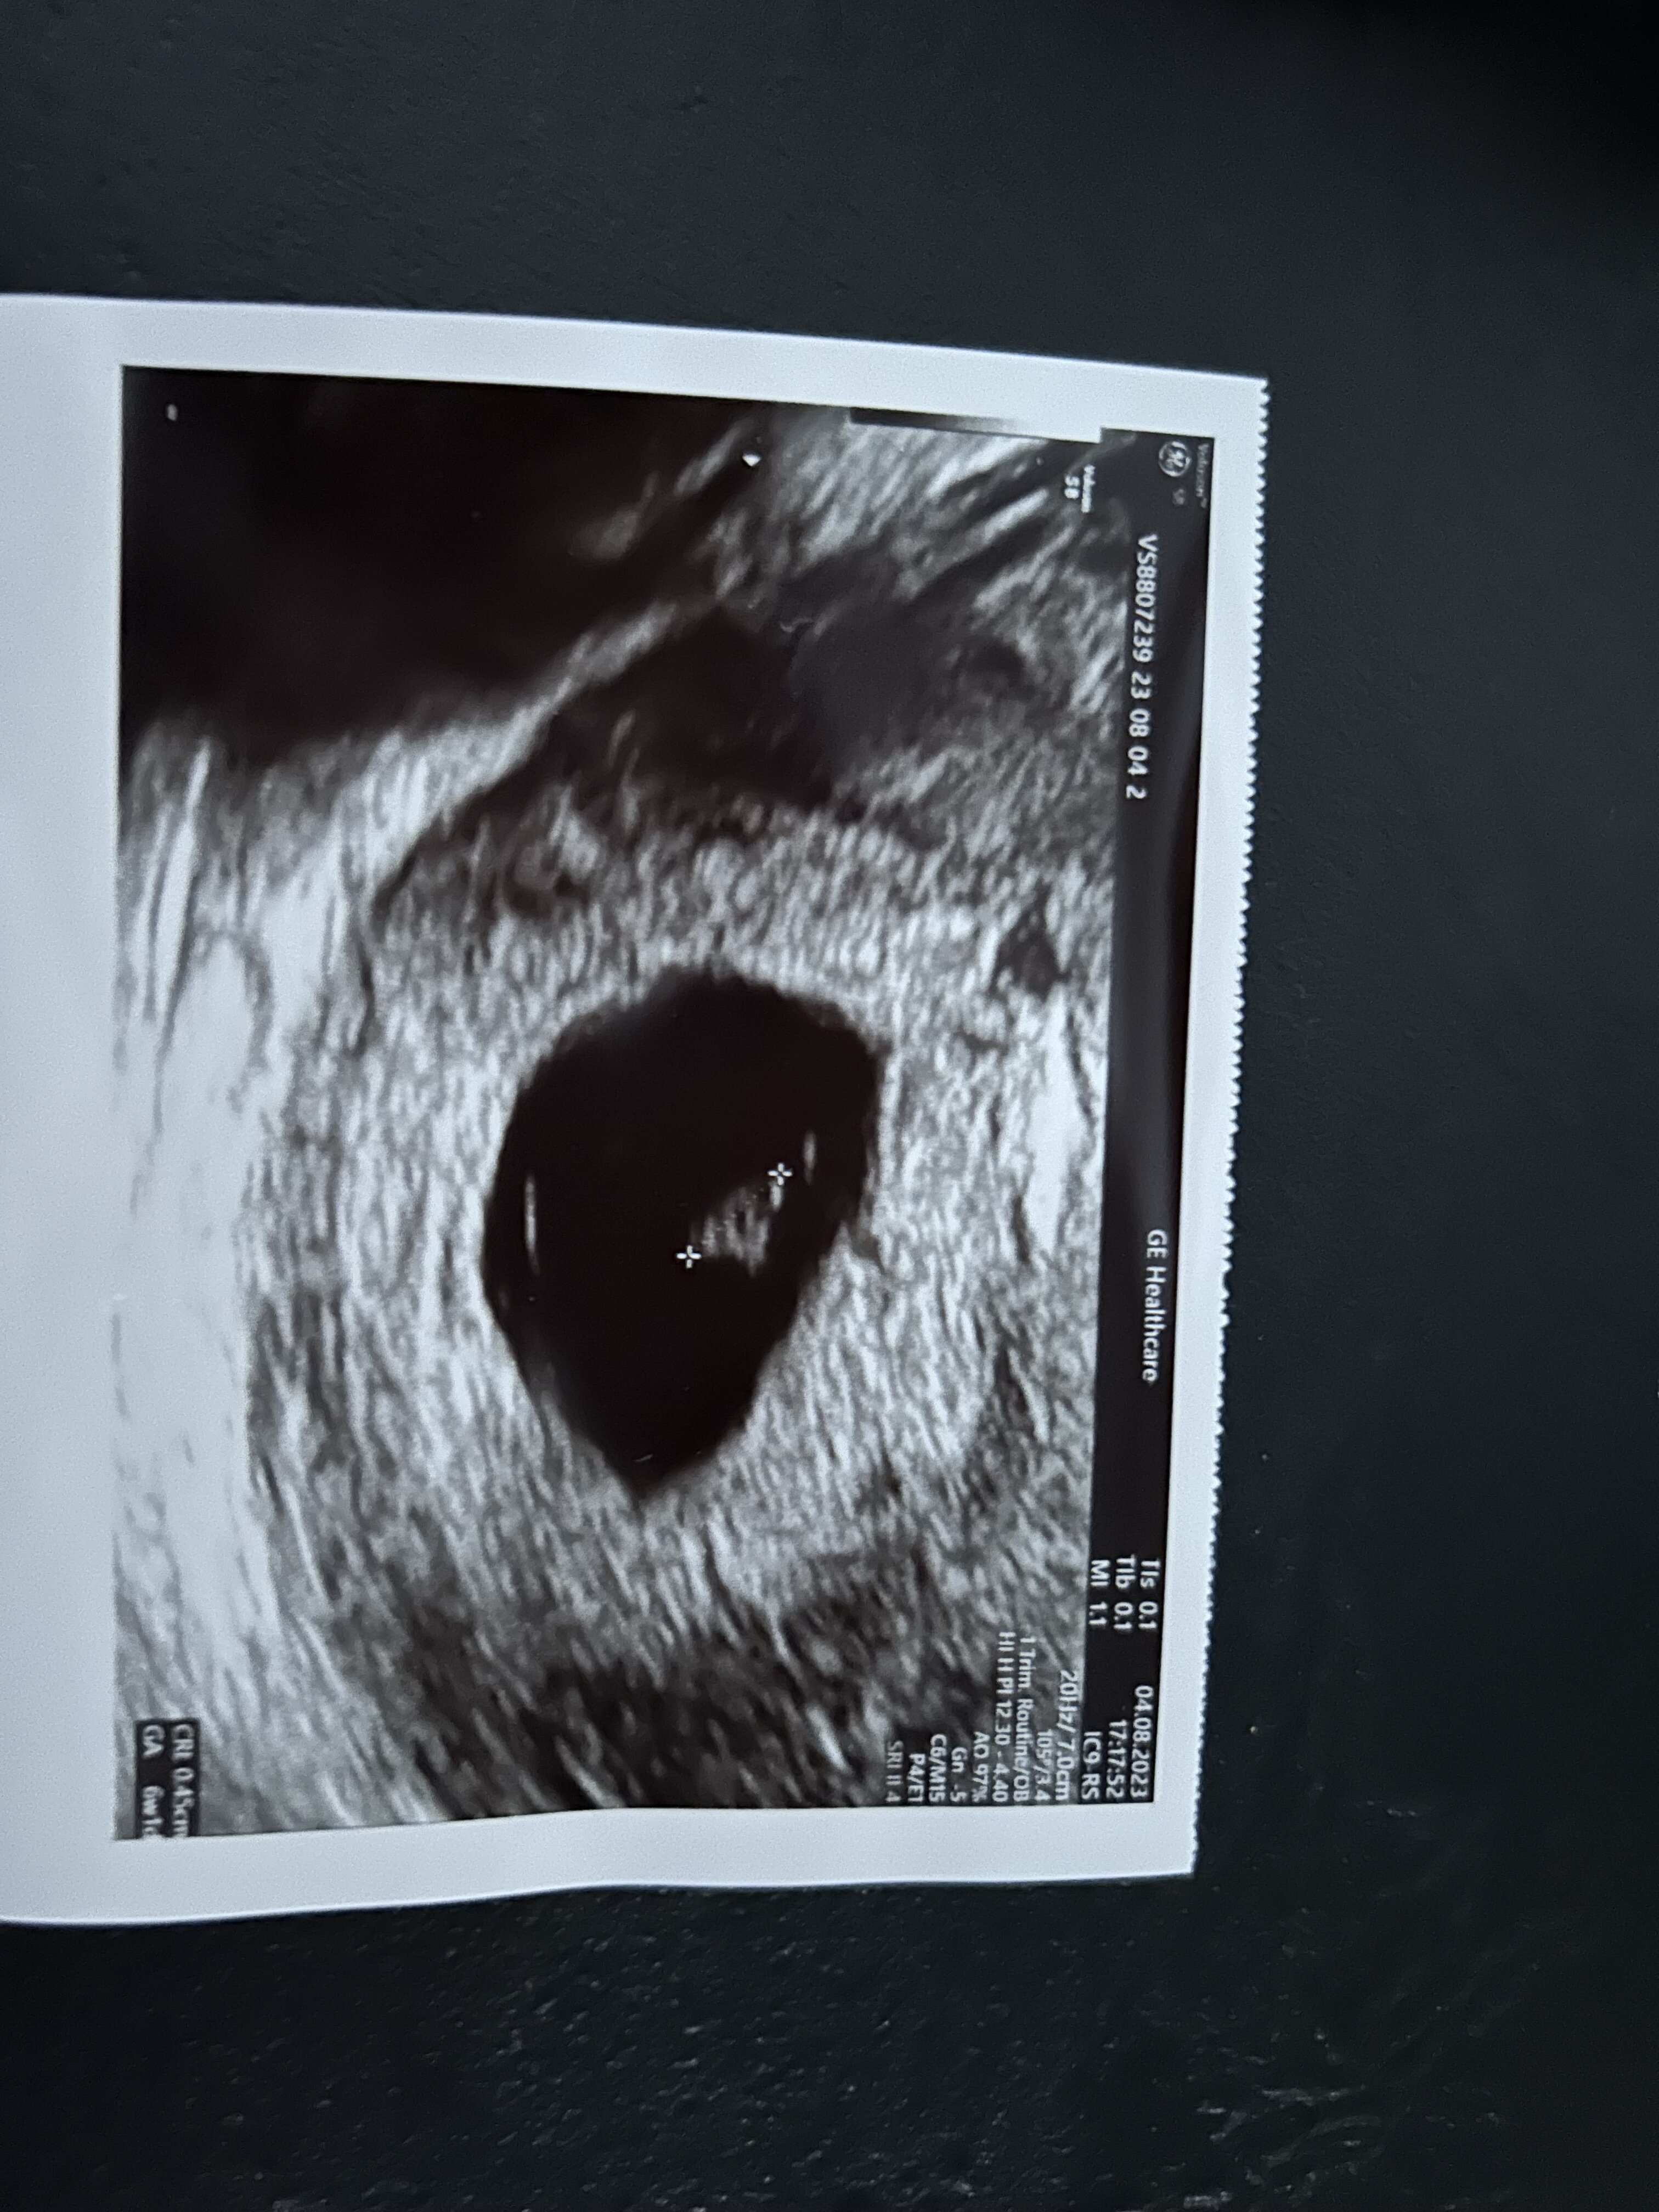

26.07 był widoczny jeden zarodek ze serduszkiem a tydzień później zarodek z wiekiem młodszym

Nie wyklucza drugie tak jak pisałam widziała dwa pecherzyki jeden przodujący mniejszy ten z zarodkiem bez serduszka oraz za nim dużo większy z pulsującym punktem

Dla tej lekarz jest to ciąża bliźniacza we wtorek idę na jeszcze jedno usg i jutro na betę

A masz może zdjęcie USG?

• IMG_3815.jpeg

IMG_3815.jpeg

981 KB · Wyświetleń: 144